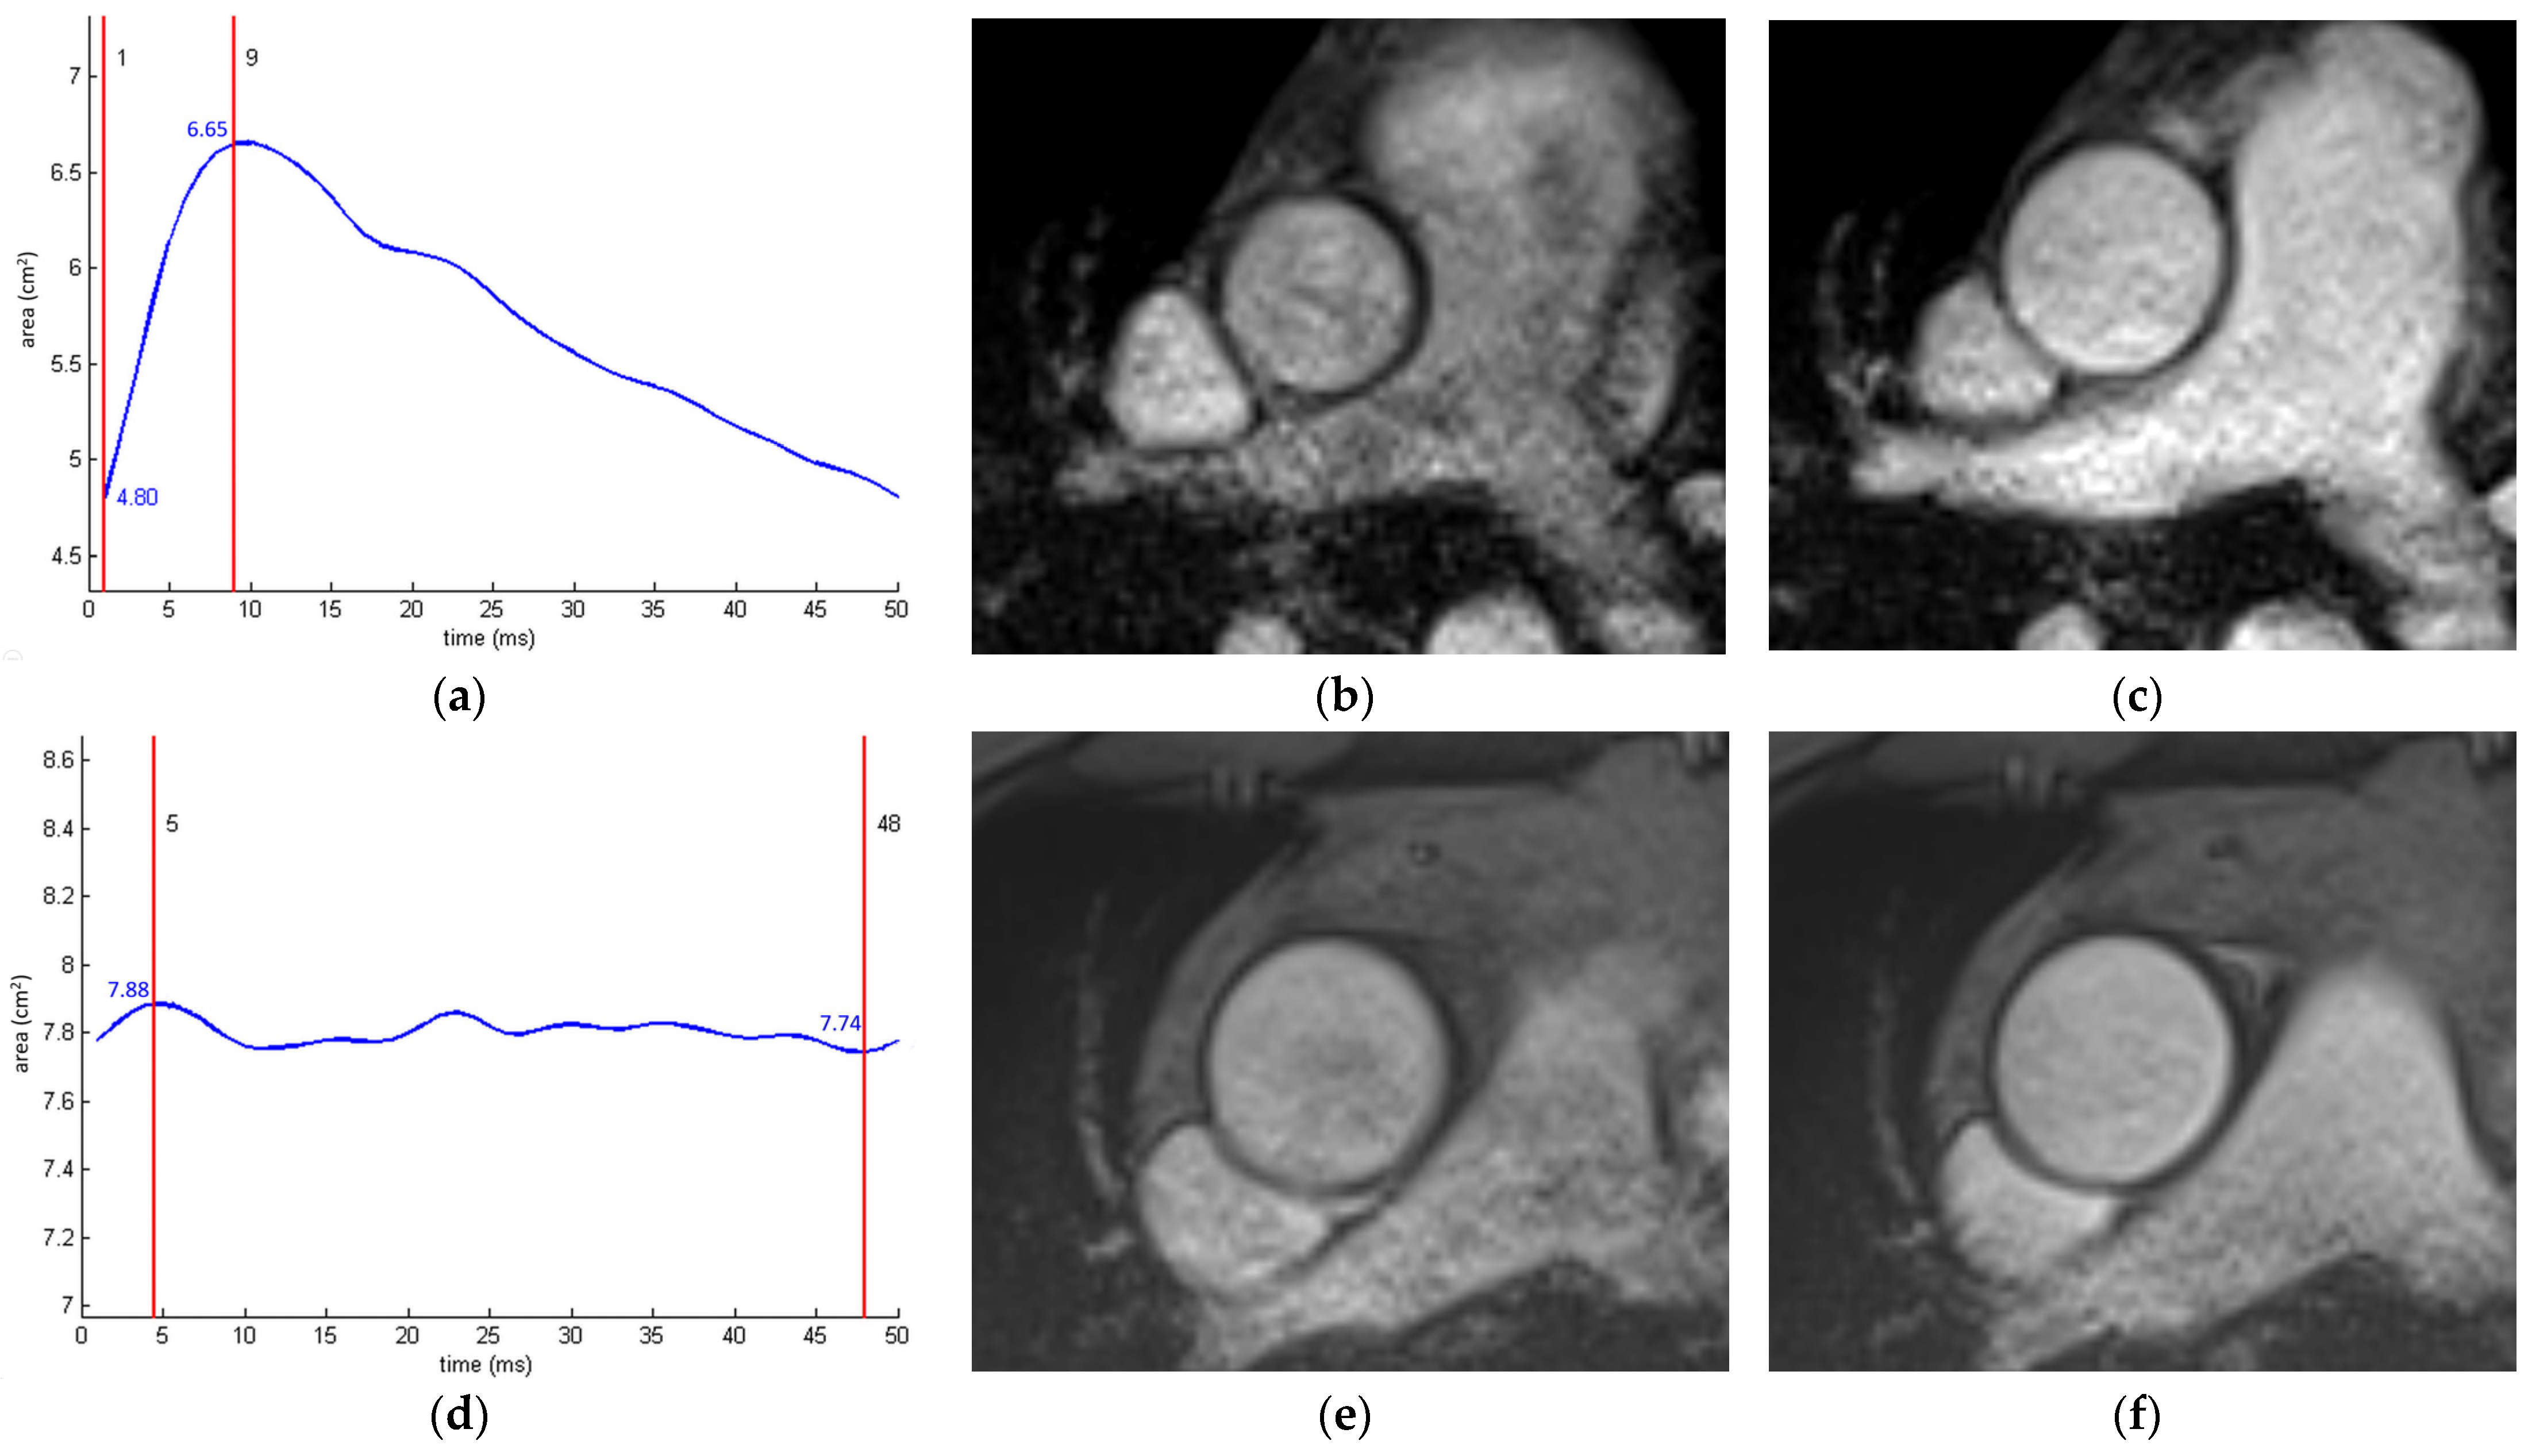

Figure 9.

Aortic strain measurement in a young (42%, (a–c)) and an old patient (2%, (d–f)). The curves created using a validated automated software ARTerial-FUNction (INSERM UMR-S 1146) [102] represent changes in the aortic cross-sectional area throughout the cardiac cycle (a,d). End-diastolic (b,e) and end-systolic (c,f) gradient-echo cine images through the ascending aorta.